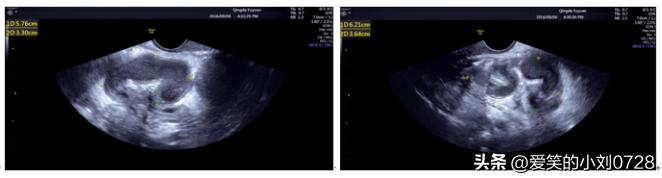

告知患者需要重新检查下血常规,并且要进行超声检查,患者同意。血常规显示:白细胞25.71*10~9/L,中性粒细胞23.64*10~9/L,说明白细胞和中性粒细胞都是升高的。妇科超声(图1)提示:右附件区5.8x3.3x3.8cm囊性包块,呈弯曲管状,内透声差,见细点样回声;左附件区探及6.2x3.6x5.8cm囊性包块,呈弯曲管状,内透声差,见细点样回声,考虑输卵管积脓。体格检查:腹部柔软,下腹深压痛,无反跳痛。妇科查体:阴道内见黄色分泌物,宫颈举痛阳性,双侧附件区压痛。

妇科超声提示:考虑输卵管积脓